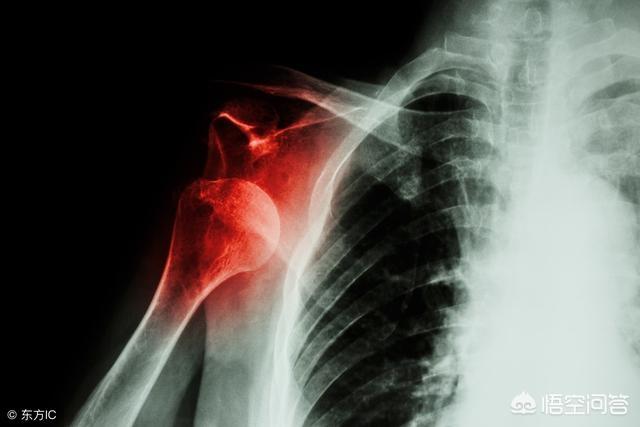

L'articulation de l'épaule comporte des structures très importantes, l'une étant l'acromion et l'autre la grosse tubérosité de l'humérus, et au fur et à mesure de l'utilisation de l'articulation de l'épaule, de l'âge ou d'éléments congénitaux, etc.Possibilité de conflit entre l'acromion et la grosse tubérosité de l'humérusIl s'agit d'une cause très fréquente de douleur à l'épaule, diagnostiquéele syndrome de l'impingement de l'épaule, qui peut généralement être déterminé à l'aide de radiographiesSur le cliché radiographique, on peut voir les marques d'impaction telles que l'hyperplasie. Vous comprendrez mieux cela en regardant l'image ci-dessous, la marque rouge est l'hyperplasie et la marque jaune est l'acromion en forme de crochet. Les marques rouges correspondent aux excroissances osseuses et les marques jaunes à l'acromion en forme de crochet.Si le conflit n'est pas soulagé et s'aggrave, il existe un risque élevé de rupture de la coiffe des rotateurs, une structure importante située entre l'acromion et la grosse tubérosité. C'est pourquoi il n'est pas recommandé aux patients souffrant d'un syndrome de conflit de l'épaule de suivre une rééducation par décharge de l'épaule en position debout.

Cependant, grâce à des recherches de plus en plus nombreuses sur l'articulation de l'épaule, il est désormais possible d'affirmer que la douleur à l'épaule a été étudiée de manière plus approfondie.L'accent est mis de plus en plus sur le traitement de la douleur à l'épaule. On ne suppose plus simplement que la douleur à l'épaule est une épaule gelée, et il arrive qu'un mauvais diagnostic soit posé et que l'on dise au patient de lancer l'épaule assez fort, ce qui peut causer des dommages, tels que des déchirures de la coiffe des rotateurs.. Voici quelques causes courantes de douleur à l'épaule pour vous donner un bref aperçu des problèmes qui peuvent être difficiles à guérir par vous-même s'ils sont les suivants.